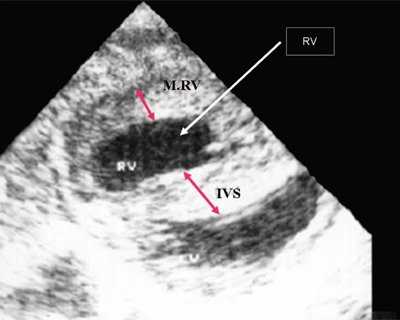

Рис. 1. Систолическая перегрузка правого желудочка. Поперечное сечение желудочков сердца при стенозе легочной артерии. Градиент давления правый желудочек - легочная артерия равен 200 мм рт.ст. Выраженная гипертрофия межжелудочковой перегородки и миокарда передней стенки правого желудочка.